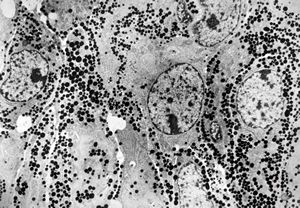

F, 72y. | carcinoid … metastasis to lymphonode